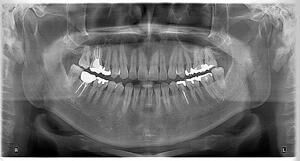

2 Boyutlu Görüntüleme (Panoramik Film)

Panoramik dental film, ağız ve çene yapısının geniş bir görüntüsünü sağlayan, diş hekimliği alanında kullanılan 2 boyutlu bir radyolojik inceleme yöntemidir. Bu film, diş hekimlerine dişlerin yanı sıra çene kemikleri, sinüs boşlukları ve çene eklemi gibi önemli anatomik bölgeler hakkında detaylı bilgi sunar. Panoramik dental film, tek bir görüntü üzerinden geniş bir perspektif sağlayarak, hastanın oral sağlık durumu hakkında kapsamlı bir değerlendirme yapılmasına yardımcı olur.